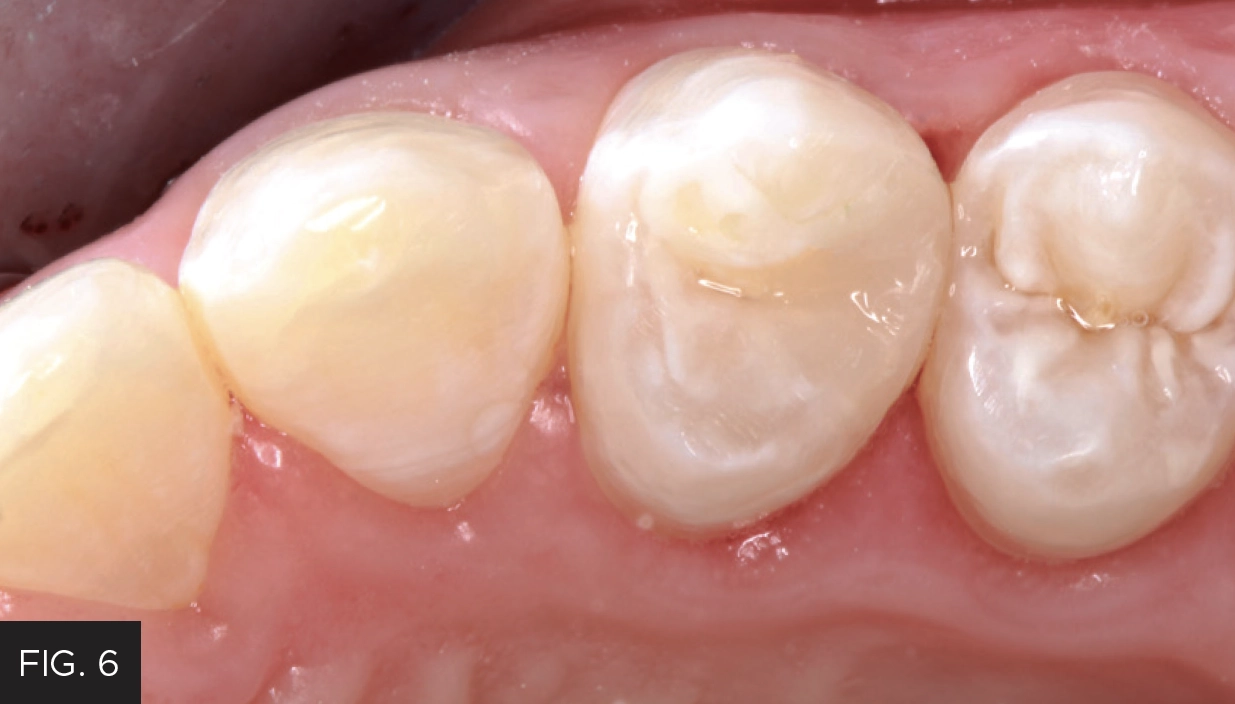

This clinical case highlights a common scenario. (FIG. 1) A Class II carious lesion was detected on the distal of #5. (FIG. 2) The patient was anesthetized via infiltration. Before preparation, a latex free rubber dam (True™ Dental Dam, Clinician’s Choice®) was placed to provide the first line of isolation.